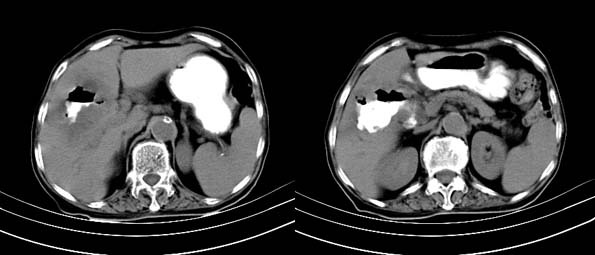

以下是引用bailaode在2008-6-12 22:10:00的发言:[br]资料中未提及患者有无急腹症体征,这个很重要。[br] ct表现:肝内境界模糊之低密度灶,内有含对比剂之液气平面.(提示肝内病灶与胃肠道沟通) [br] 1、根据“长城干红 ”所提供的资料“患者,女,74岁,黑便月余,消瘦,一般状况差,白细胞1万四千”,是否可认为是个慢性病程?那么我首先考虑:十二指肠结核,十二指肠--胆管瘘,继发胆道逆行感染肝脓肿形成。[br] 2、如有急腹症体征则考虑:十二指肠溃疡穿孔?十二指肠占位伴穿孔?

以下是引用拾荒者在2008-6-13 22:13:00的发言:[br]病灶与升结肠、肝脏及十二指肠关系密切,且结肠降段见造影剂影,支持结肠与十二指肠瘘形成,原因及原发病在哪不好定,不过,虽说有风险,但还是应该手术治疗,单纯抗感染估计不行。